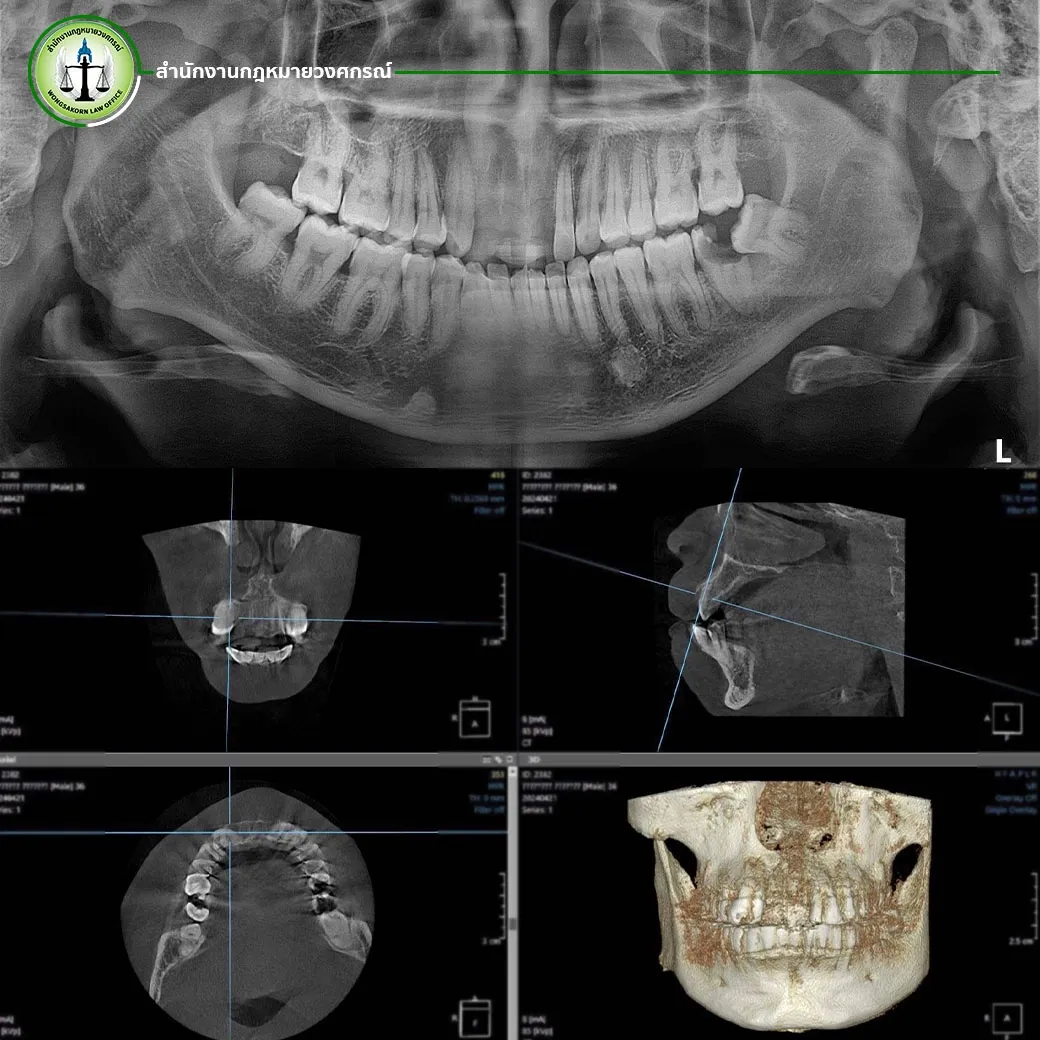

ในสถานการณ์ที่เลวร้ายแบบนี้ แต่ความเจ็บปวดและความทุกข์ทรมานของนาย A กลับไม่ได้รับการเยียวยาอย่างที่ควรจะเป็น เมื่อบริษัทประกันภัยหัวแพทย์พิจารณาชดใช้ค่ารักษาฟันที่ต้องสูญเสียรากฟันไปให้เพียง 30,000 บาทเท่านั้น ซึ่งเป็นจำนวนเงินที่ห่างไกลจากค่ารักษาจริงที่ทันตแพทย์ประเมินไว้เป็นอย่างมาก เนื่องจากนาย A ได้รับการประเมินค่ารักษาพยาบาลจากทันตแพทย์อย่างละเอียด โดยทันตแพทย์ระบุว่าความเสียหายของฟันแต่ละซี่นั้นมีมูลค่าการรักษาสูงถึง 85,000 บาทต่อซี่ สาเหตุเพราะรากฟันได้รับความเสียหายอย่างมาก ซึ่งสามารถเห็นได้ชัดเจนจากฟิล์มเอกซเรย์